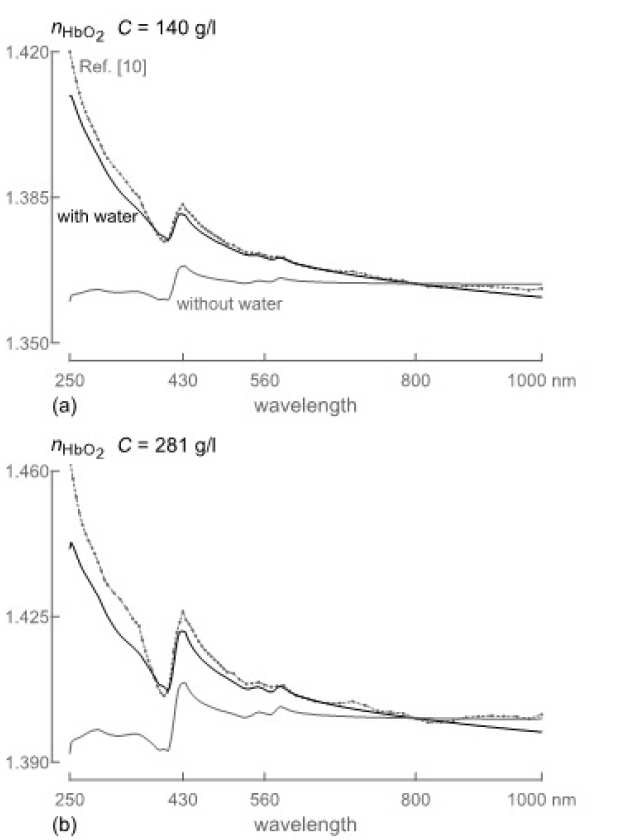

Because the refractive index of hemoglobin in the visible range is sensitive to the hemoglobin concentration, optical investigations of hemoglobin are important for medical diagnostics and treatment. Direct measurements of the refractive index are, however, challenging; few such measurements have previously been reported, especially in a wide wavelength range. We directly measured the refractive index of human deoxygenated and oxygenated hemoglobin for nine wavelengths between 400 and 700 nm for the hemoglobin concentrations up to 140 gl−1. We analyzed the results and suggested a set of model functions to calculate the refractive index depending on the concentration. At all wavelengths, the measured values of the refractive index depended on the concentration linearly. Analyzing the slope of the lines, we determined the specific refraction increments, derived a set of model functions for the refractive index depending on the concentration, and compared our results with those available in the literature. Based on the model functions, we further calculated the refractive index at the physiological concentration within the erythrocytes of 320 gl−1. The results can be used to calculate the refractive index in the visible range for arbitrary concentrations provided that the refractive indices depend on the concentration linearly.

| Refractive index of oxygenated and deoxygenated haemoglobin (a) measured and (b) calculated at different haemoglobin concentrations |

O. Sydoruk (in collaboration with Erlangen-Nuremberg University and Saratov University)

Because direct measurements of the refractive index of hemoglobin over a large wavelength range are challenging, indirect methods deserve particular attention. Among them, the Kramers-Kronig relations are a powerful tool often used to derive the real part of a refractive index from its imaginary part. However, previous attempts to apply the relations to solutions of human hemoglobin have been somewhat controversial, resulting in disagreement between several studies. We showed that this controversy could be resolved when careful attention is paid not only to the absorption of hemoglobin but also to the dispersion of the refractive index of the nonabsorbing solvent. We developed a Kramers-Kroning analysis taking both contributions into account and compare the results with the data from several studies. Good agreement with experiments is found across the visible and parts of near-infrared and ultraviolet regions. These results reinstated the use of the Kramers-Kronig relations for hemoglobin solutions and provide an additional source of information about their refractive index.

| Comparison between refractive indices calculated using different models at different concentrations. |